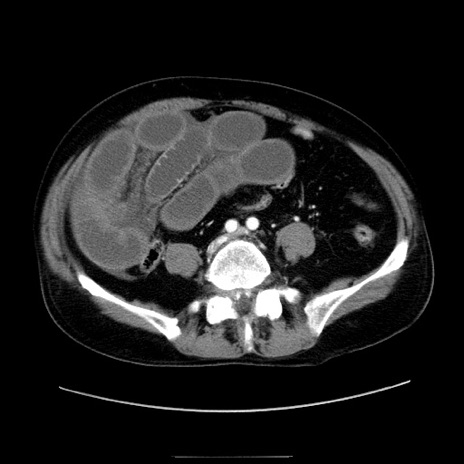

症例30(横断像)

【症例】80歳代男性

【主訴】臍周囲痛

【現病歴】約6時間前から臍下部痛が出現。次第に腹部膨隆・背部痛も生じてきたため来院。背部痛の場所は変化しない。

【身体所見】意識清明、BT 36.3℃、BP  131/87mmHg、P 87bpm、SpO2 100%(RA)、臍周囲自発痛・圧痛あり、反跳痛なし、自発痛部位に一致して板状硬あり、腹部膨隆、腸雑音減弱、CVA tenderness両側陰性。

【データ】WBC 19600、CRP 0.33